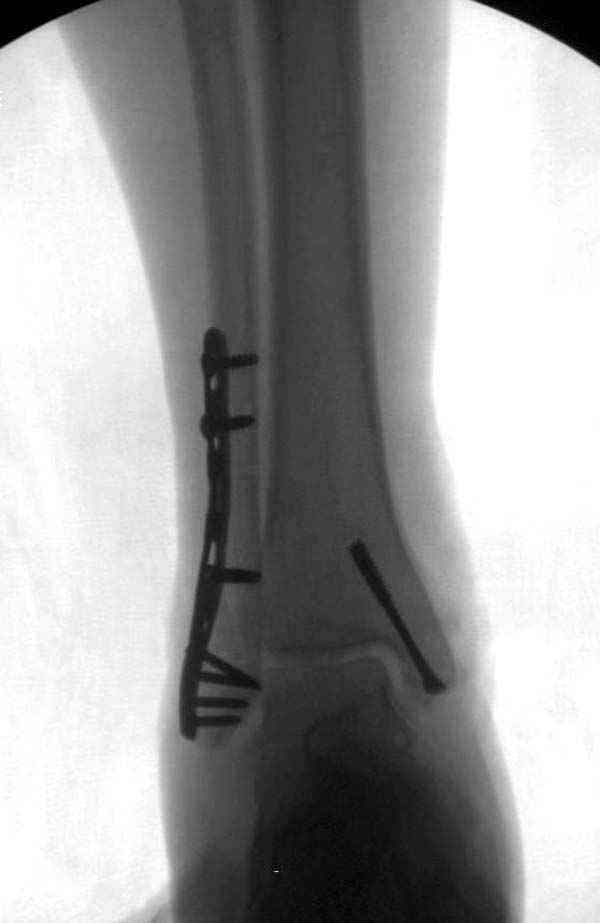

Случай прошлого года:пациентка-молодая ,крупная женщина ,30лет.Травма в начале апреля 2009г-пронационный перелом лодыжек с подвывихом стопы.Ко мне обратилась через 35 дней,прооперирована 22.05.2009г.Внутренняя лодыжка фиксирована по Веберу,наружная реконструктивной пластиной с наложением болта-стяжки.Иммобилизация "сапожок" в течении месяца,затем пригипсовано "стремя".Гипс снят 10.07.2009г

Достаточно быстрое восстановление функции.В октябре 2009г-почувствовала боль,в области рубца над гайкой открылся свищ.На Р-граммах-консолидация переломов и смещение гайки по стяжке.10.11.2009г-конструкции удалены,санация,заживление ран.В настоящее время пациентку ничего не беспокоит.На операции-раскручивание гайки-болталась на конце стяжки.Вопросы:какой механизм раскручивания и что я неправильно сделал?Свои версии:1)в области синдесмоза успела образоваться рубцовая ткань,которая при движении в суставе"пружинила",поскольку голеностопный сустав является спиральным, то и биомеханика подобна кривошипному механизму.2)Реконструктивная пластина не "реконструировалась" по форме лодыжки.Наложил,как есть.То есть подпружинивала сама пластина.Ну,это мои догадки.Что нужно,чтобы избегать впредь таких,пусть и не "страшных"осложнений:Рассверливать через лодыжку область синдесмоза?Ставить шайбу-гровер?Тщательно моделировать пластину?Прилагаю сравнительные снимки-сразу после операции и перед удалением конструкции.

Визуально никаких вопросов по репозиции не было.Да и на основании чего сомнения,что наружная лодыжка не полностью репонирована или прорезалась проволка ???Я не вижу...Снимок после репозиции справа.

Раз ,есть желание посмотреть другую проекцию выкладываю-ну лучшего качества нет...